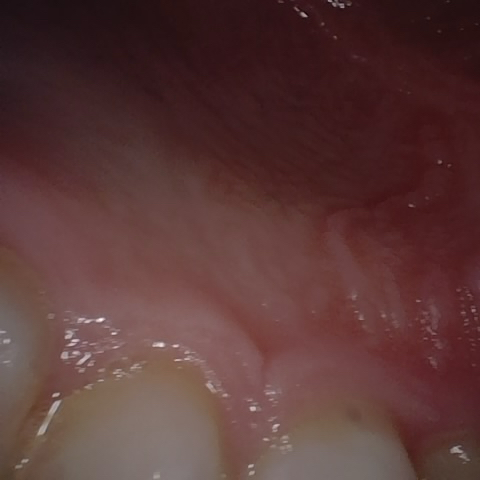

Annotated as "Good"